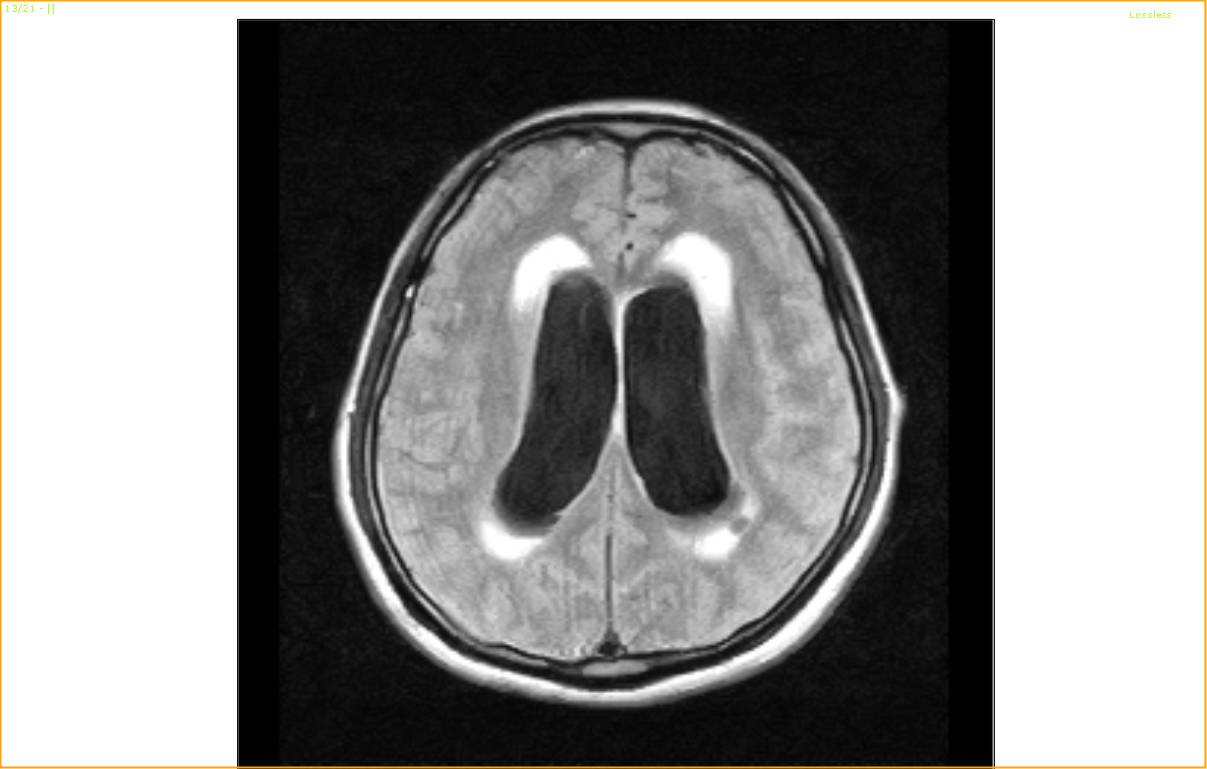

I proceeded to do an MRI of the Brain:

A huge Mass over the upper part of Midbrain causing Obstructive Bilateral Hydrocephalus………………………….